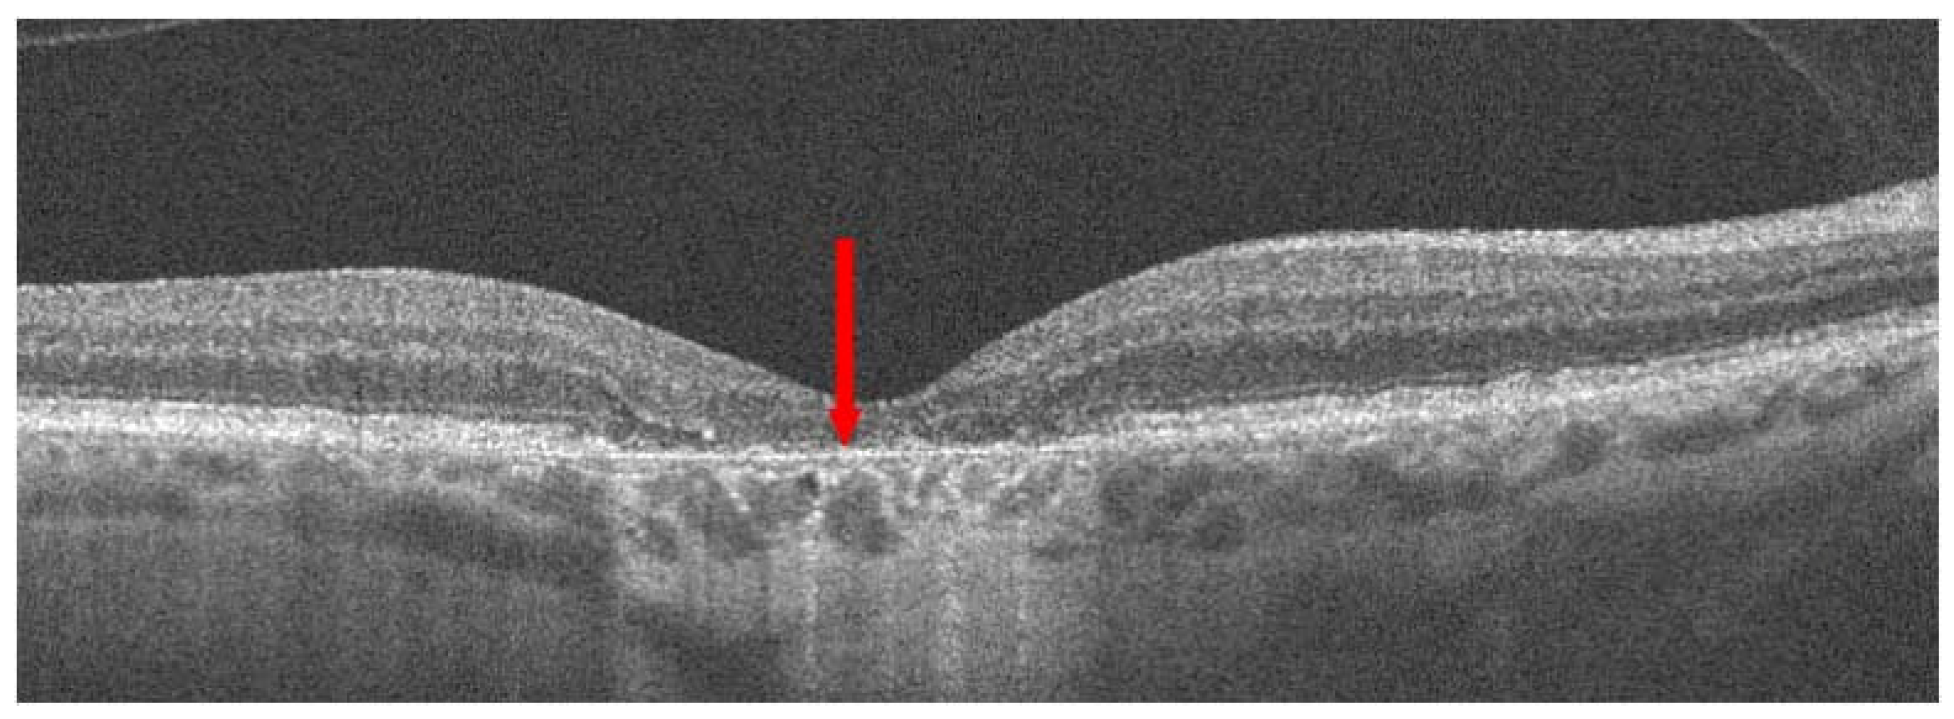

- Spaide, R.F.; Jaffe, G.J.; Sarraf, D.; Freund, K.B.; Sadda, S.R.; Staurenghi, G.; Waheed, N.K.; Chakravarthy, U.; Rosenfeld, P.J.; Holz, F.G.; et al. Consensus Nomenclature for Reporting Neovascular Age-Related Macular Degeneration Data: Consensus on Neovascular Age-Related Macular Degeneration Nomenclature Study Group. Ophthalmology 2020, 127, 616–636. [Google Scholar] [CrossRef]

- Hilely, A.; Au, A.; Freund, K.B.; Loewenstein, A.; Souied, E.H.; Zur, D.; Sacconi, R.; Borrelli, E.; Peiretti, E.; Iovino, C.; et al. Non-neovascular age-related macular degeneration with subretinal fluid. Br. J. Ophthalmol. 2021, 105, 1415–1420. [Google Scholar] [CrossRef]